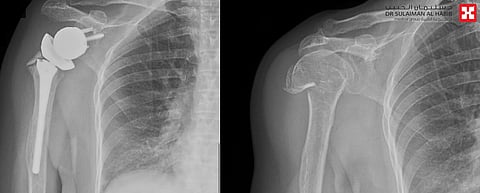

نجح فريق طبي متخصص في جراحة العظام بمستشفى الدكتور سليمان الحبيب بالسويدي، في إجراء عملية استبدال مفصل الكتف باستخدام تقنية مفصل الكتف المعكوس "Reverse shoulder arthroplasty"، لمريضة سبعينية كانت تعاني من كسر متبدل، وتقطع في أوتار الكتف الأيمن.

وقال د.ناصيف فرح استشاري جراحة العظام ورئيس الفريق الطبي المعالج: راجعت المريضة المستشفى مشتكية من آلام شديدة في الكتف استمرت معها لسنوات، مع عدم قدرتها على رفع الكتف أو استخدام اليد المصابة في أداء مهامها اليومية الاعتيادية، وخضعت للكشف السريري والأشعة السينية وأشعة الرنين المغناطيسي، وكشفت النتائج وجود احتكاك شديد في مفصل الكتف نتيجة تمزق العضلات، وأجريت لها عملية جراحية لتبديل المفصل المصاب بآخر معكوس، وتم فيها تنظيف محيط المفصل القديم من التكلسات والزوائد العظمية المسببة للاحتكاكات، ومن ثم تركيب المفصل الصناعي الجديد، الذي يتميز بجودته العالية ويساعد في تحقيق المرونة الكاملة للمفصل ومجال أكبر من الحركة.

وأضاف د.ناصيف أن الجراحة التي استمرت لنحو ساعتين، تكللت بالنجاح التام، وتم تحويل المريضة إلى جناح التنويم بحالة صحية جيدة، وتَمَكنت المريضة -بحمد الله- بعد خضوعها لـ"10" جلسات من العلاج الطبيعي، من استعادة قدرتها على تحريك الكتف، واستخدامه للأنشطة اليومية، إضافة إلى أنها تخلصت من الآلام بشكل نهائي وغادرت المستشفى بعد 3 أيام من العملية.